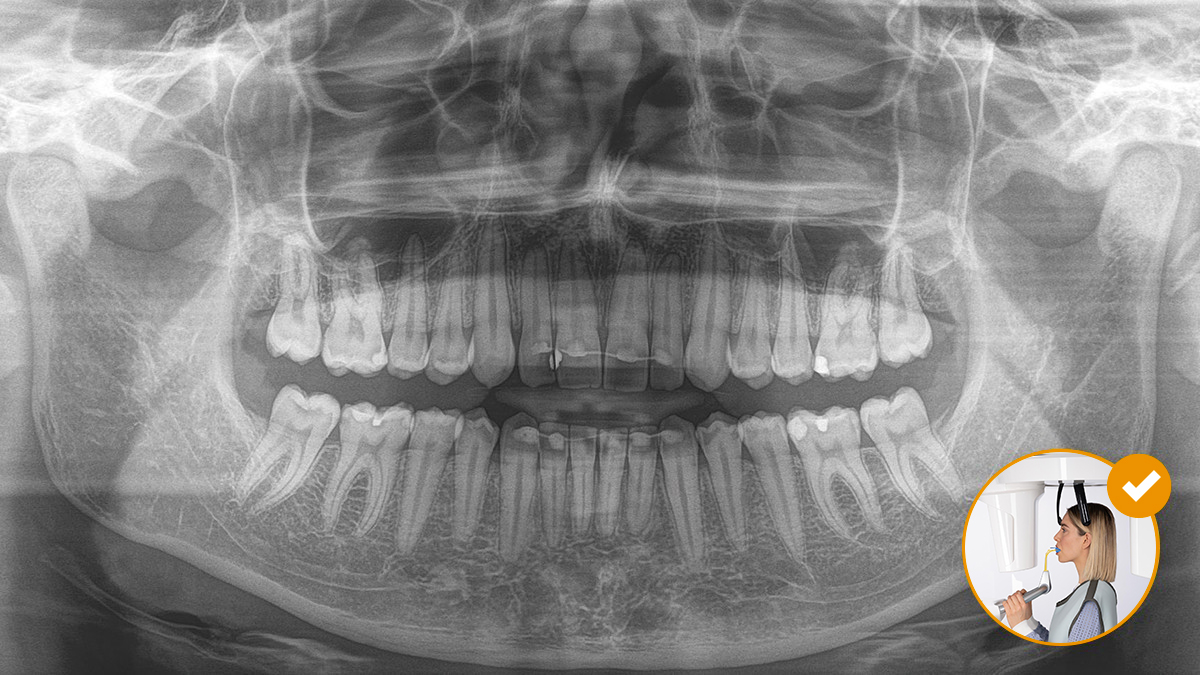

Ein entspanntes und angenehmes Vorgehen ist für alle gleichermaßen wichtig, für die Patienten wie für das Personal. Es ist zufriedenstellend und motivierend, wenn alles nach Plan läuft und die Dinge reibungslos funktionieren. Die Verwendung von Orthophos oder Axeos mit Sidexis 4 bietet Ihnen gezielte Unterstützung. Die Röntgensysteme sind einfach zu bedienen, aber einzigartig in ihren Diagnosemöglichkeiten. Dadurch wird sichergestellt, dass jeder Aspekt des Behandlungsprozesses eine positive Erfahrung darstellt.

Die korrekte Patientenpositionierung führt zu einer hohen Bildqualität, die eine genaue Diagnose ermöglicht und die Patientenerfahrung erleichtert und verbessert.

Dies ist unser 10-Punkte-Konzept für die einfache Patientenpositionierung und Röntgenbildgebung. Es geht in erster Linie um zwei Dinge: Hochwertige Aufnahme und Komfort für den Patienten und die Assistenten.